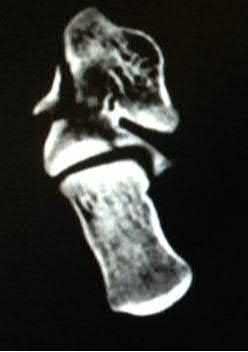

A 26-year-old male sustains an elbow injury after a fall from a skateboard resulting in valgus and supination forces across the left elbow. A CT scan of the left elbow is shown in Figures A through D. This fracture pattern is most commonly associated with what other traumatic elbow pathology?

The clinical presentation is consistent with a coronoid tip fracture. This fracture pattern is associated with a radial head fracture and posterolateral ulnohumeral dislocation - together making up the terrible triad injury.

A terrible triad injury is the result of a valgus and supination injury and involves posterolateral elbow dislocation or lateral collateral ligament injury, radial head fracture, and fracture of the coronoid process. The elbow may dislocate postero-laterally with the anterior bundle of the MCL intact, but if the MCL is injured it is typically the last structure to fail. The coronoid fracture is typically a small fragment isolated to the tip. This is a result of a posteriorly directed force driving the coronoid into the trochlea prior to posterior elbow dislocation. CT scan is a useful modality when small or comminuted fragments are difficult to visualize on plain radiographs.

Figures A through D show consecutive 2.00 mm sagittal CT reformats demonstrating a small coronoid fracture fragment which was addressed with suture fixation.